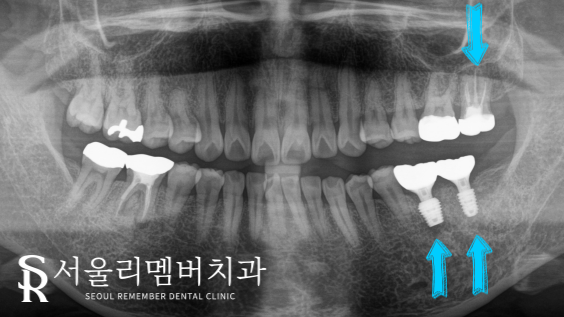

자 완성된 모습을 살펴볼까요?

이전과는 달리 튼튼한 임플란트가

아래 어금니에 자리를 잡고 있었으며,

신경치료 또한 성공적으로 마무리된 것을

볼 수 있었습니다.

다행히 계획했던 대로 마무리가 잘 되었는데요.